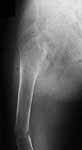

A male 23 y.o. many years sustained severe osteoporosis with multiple fractres of long bones and ribs. Last 4 years was not able to leave chair. Some x-rays attached. What may cause the situation? Juvenile osteoporosis should have been recovered spontaneously to date. What lab research is needed? What is most likely diagnosis? Can such fractures be treated more aggressively? What medications can improve bone quality? Biphosphonates? Somatotropin?